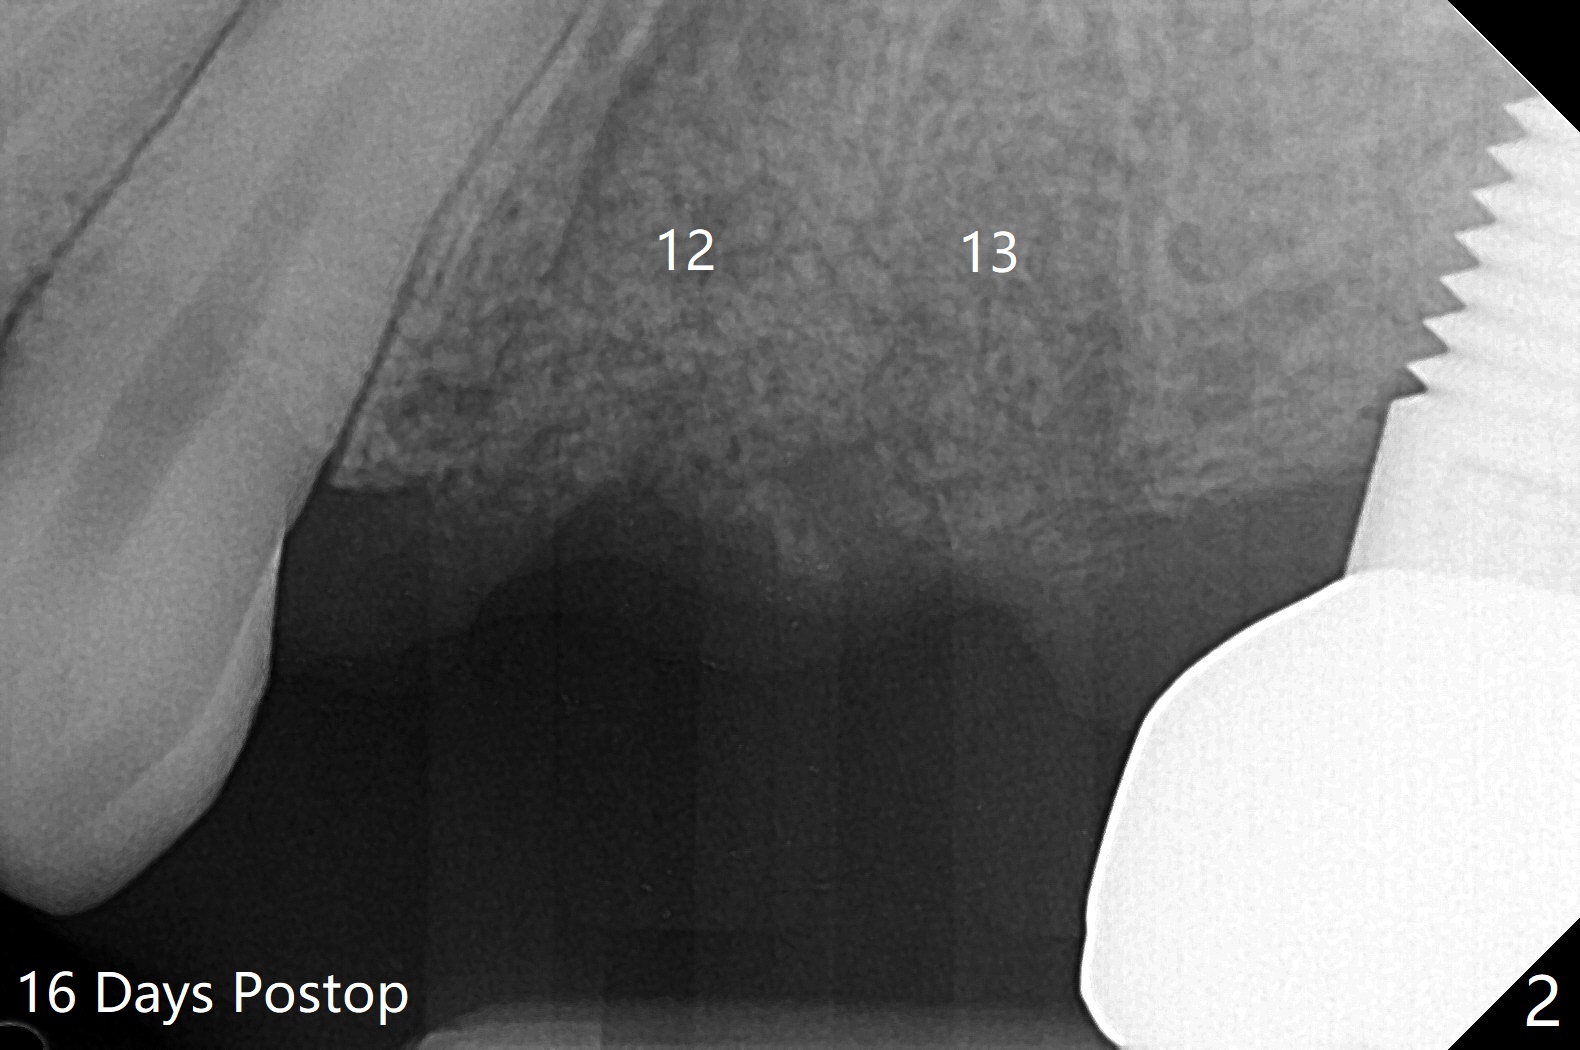

42岁女,12号牙断裂(图一),在拔除中不幸损伤13号牙,一起拔除,用GEM21S与异体骨和人工骨进行位点保存,术后骨粉一直脱落,病人觉得伤口有臭味。术后16天根尖片显示骨粉仍在牙槽窝(图二),伤口尚未愈合(图三),骨粉密度不高(图四,五)。讨论后,决定去除余留骨粉,重新刮拔牙槽窝,反复冲洗,最好放置粘性骨粉(图六),覆盖PRF和不可吸收膜,使用PTFE缝线,树脂敷料。术后三周膜和骨粉仍在原位(图七,八)。为了恢复龈乳头,术后四,五个月,利用导板去除两个牙位牙槽嵴骨质(图九),把植体植入牙槽嵴深部,之间便形成突起的牙槽嵴(图十:C)以及龈乳头。植牙整合后,利用临时牙冠,反复调整,挤压形成比较正常龈乳头。